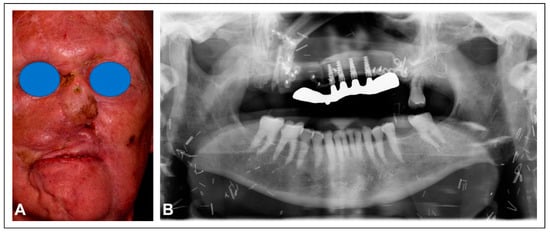

Figure 5. Frontal view of the patient status-post fibula free flap reconstruction of the mid-face (A). Panoramic radiographic of fibula reconstruction and implant rehabilitation with titanium framework (B). Surgical reconstruction to re-establish the stable base of the maxilla with an implant-supported fixed dental prosthesis provides optimal functional recovery to the patient.

The patient underwent reirradiation for orbital squamous cell carcinoma (SCC) with a second course of proton therapy (Figure 4). Despite the intervening radiation therapy, dental rehabilitation was successfully achieved with dental implants placed into the fibula flap (Figure 5).